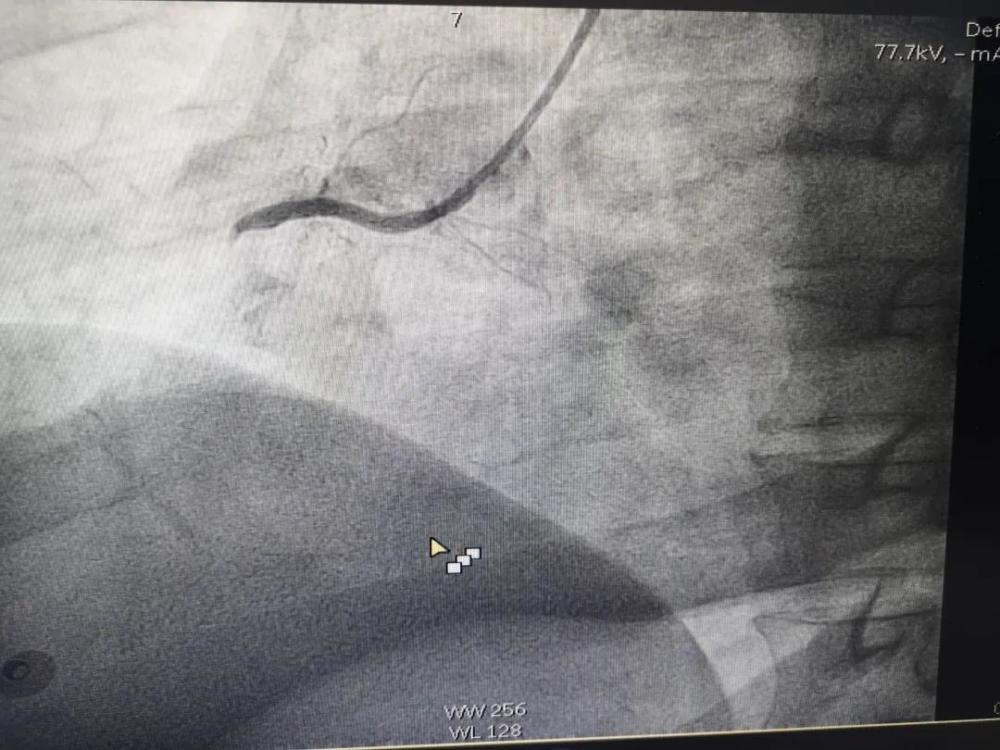

M老师在昏迷中 , 在各种仪器设备的强力生命支持条件下 , 由心血管介入团队对其完成了急诊冠脉造影检查——心脏右侧冠状动脉完全堵塞 , 伴有大量血栓形成 。 这是急性心肌梗死 , 需要马上手术开通血管 。

文章插图

堵塞的血管